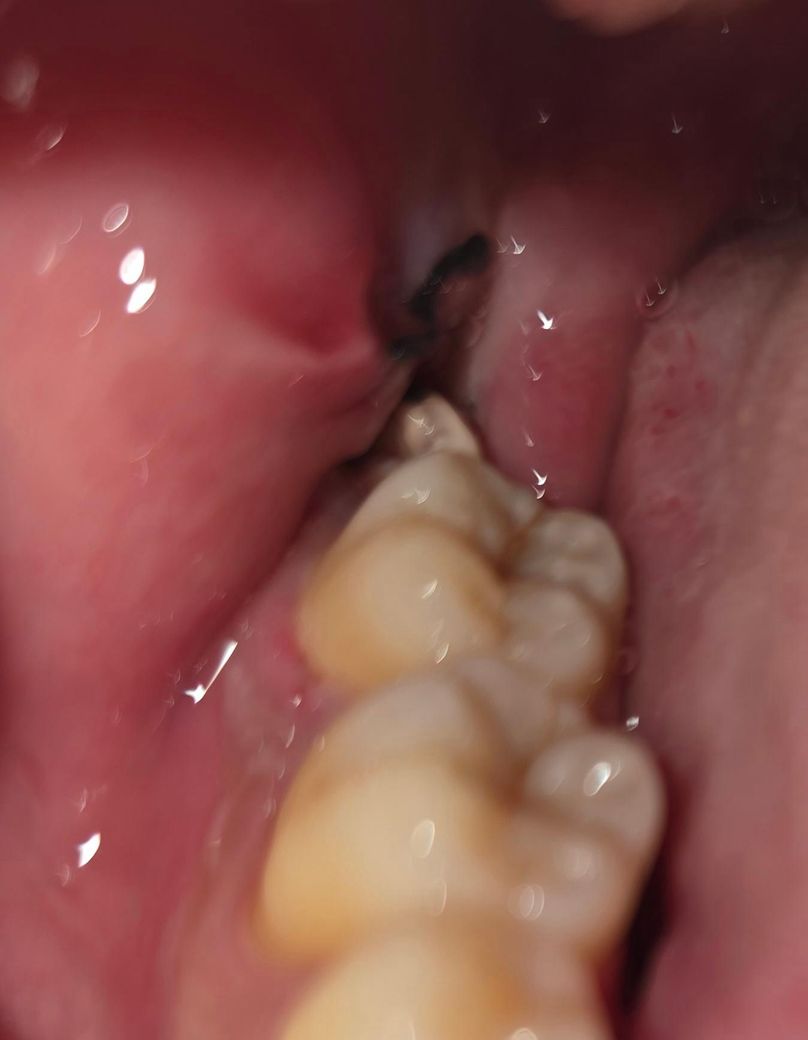

사랑니 발치한 지는 3일 됐습니다. 발치한 곳에 이상한 돌같은게 있는데 냄새가 진짜 너무 고약하고 이물감이 심해서 빼고싶은데 이게 뭘까요? 아프진 않습니다.. 냄새가 너무심해서 숨만쉬어도 나는거같아요

• 1번 째 사진